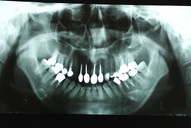

下のレントゲンの真ん中の欠けた歯が痛くて来られました。

DSC_0010

虫歯というばい菌を除去して壁を作り歯のような形にしてから根幹治療をしないと痛くなりやすいのです。

まあ、これだけでなくて治療の技術的なうまさも必要ですが、“基本”が大事なのです。そしてゴムで隔離して(ラバーダム防湿)“唾”の中のばい菌が侵入しないようにして治療をしなければなりません。歯科医院がやらない理由は保険でやると無料でやらなければならないからとか時間がないからなのです。